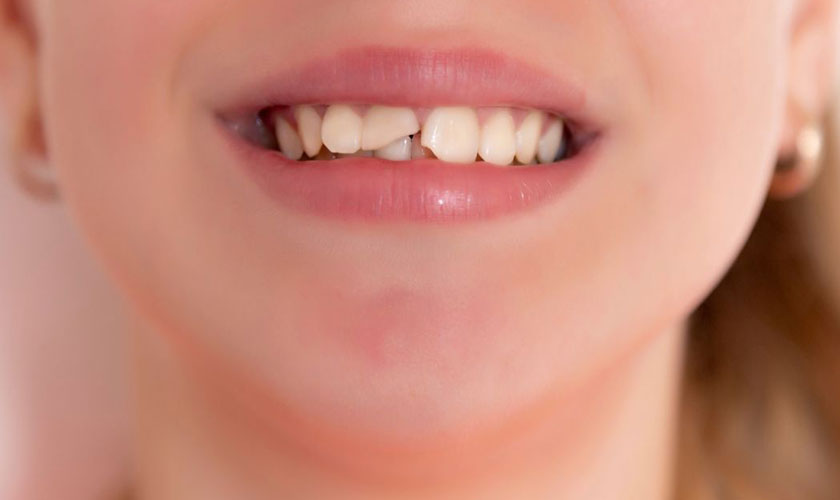

- Xuất hiện vết ố màu nâu hoặc đen: Khi tình trạng sâu răng nhẹ tiến triển, các đốm trắng dần chuyển thành vết ố màu nâu hoặc đen. Đây là dấu hiệu cho thấy men răng đã bị tổn thương nghiêm trọng hơn. Các vết ố này có thể tạo thành các lỗ nhỏ trên bề mặt răng.

- Ảnh hưởng thẩm mỹ: Sâu răng nhẹ tạo ra những vết ố, lỗ nhỏ trên răng làm giảm vẻ đẹp của nụ cười. Nếu xuất hiện ở vùng răng trước, điều này có thể ảnh hưởng đến sự tự tin khi giao tiếp.

- Phát hiện lỗ hoặc vết nứt trên răng: Khi phát hiện các vết nứt hoặc lỗ trên răng, đây là dấu hiệu rõ rệt của sâu răng hoặc tổn thương nghiêm trọng đến men răng, cần được điều trị sớm.